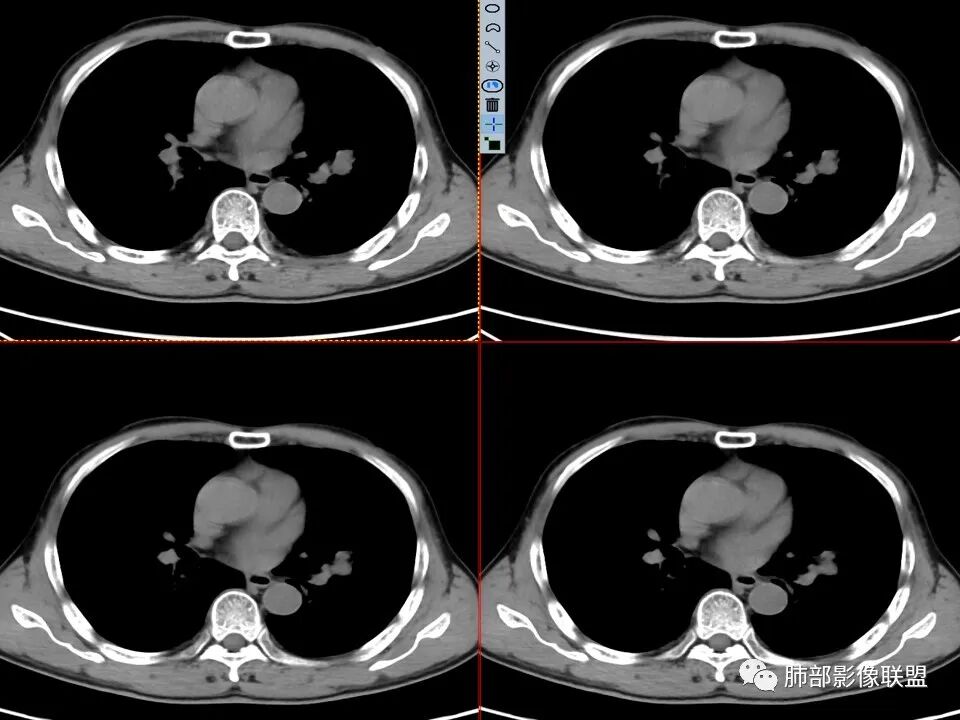

年龄不详,推测中老年人,因全身乏力就诊,CT发现左肺上叶结节灶,无明显咳嗽、发热等症状,无吸烟病史,配偶曾患“肺结核”,化验检查痰结核菌涂片阴性,CYFR轻度升高,PET-CT局部高摄取。

左肺上叶舌段近肺门区不规则结节,密度较均匀,结节边缘平直为主,可见粗短毛刺、毛刺偏软,浅分叶,收缩力不强,膨隆也不明显,周围可见模糊GGO,病灶内部支气管显示不清,病变远端支气管明显扩张,病灶与叶间裂呈宽基底相连,见刀切征,并见叶间裂多发结节影,叶间裂未见明显移位。

患者推测中老年人,无明显临床症状,肺气肿背景不明显,虽然病灶整体炎性征象较多,叶间胸膜多发结节,常规要考虑结核和腺癌,PET-CT肿瘤和炎性病变都可以高摄取,敏感性高,但特异性不高,而且腺癌周围缺乏清晰的磨玻璃及收缩力不强,故暂不考虑;虽然左肺上叶舌段病灶与支气管关系密切,如果周围磨玻璃推测为早期的阻塞性炎症,还有CYFR轻度升高,鳞癌不能除外,但是病灶的整体形态比较符合炎性改变。本病例可惜未行CT增强扫描,无法观察结节的强化特点及病灶内血管走行情况。